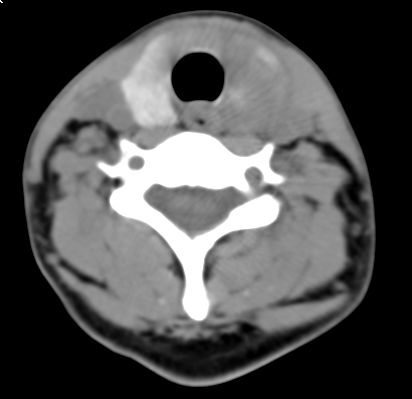

标题: CT9717:F、30Y、颈部左侧包块半年,压痛.患者拒绝作增强。 [打印本页]

标题: CT9717:F、30Y、颈部左侧包块半年,压痛.患者拒绝作增强。

请各位老师帮忙看看左侧甲状腺病灶!

甲状腺弥漫增大,以左叶明显,内见不均匀低密度影,边缘模糊欠清,周围脂肪间隙模糊。

结合病史:考虑亚急性甲状腺炎可能性大。(不知道病人有没有检测tsh t3 t4)

左侧甲状腺及甲状腺狭部弥漫性增大,边缘模糊,未见明确界线.考虑甲状腺炎可能性大.

甲状腺弥漫增大,以左叶明显,左侧内见不均匀低密度影,边缘模糊欠清,周围脂肪间隙模糊。

1,病灶弥漫无明确边界.2,密度较均质.3,临床压痛明显.

2,亚急性甲状腺炎.临床多见,发病年龄较轻,由上呼吸道感染或病毒性腮腺炎后发病.临床触痛明显.然局部皮肤无红热.t3t4早期升高,后期降低.病灶可单侧或双侧.易炎性渗出,使脂肪密度增高.